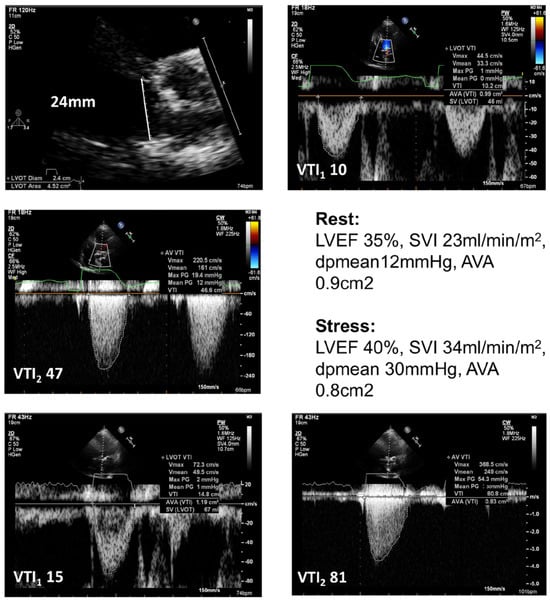

Figure 1.

Illustration of findings in true severe low-flow low-gradient aortic sternosis during low-dose dobutamine stress echocardiography. Top and middle row – findings at rest. Bottom row – findings during low dose dobutamine stress (20μg/kg/ min). Findings indicate contractile reserve and severe stenosis.

Low-Flow-Low-Gradient Aortic Stenosis (LF-LG-AS) with reduced LVEF (<50%)

LF-LG-AS with reduced LVEF is defined by an aortic valve area (AVA) <1 cm2, a maximal flow velocity (Vmax) <4 m/s, and a mean AVPG <40 mmHg in case of a reduced left ventricular systolic function. This can be due to a true severe AS, or due to a pseudo-severe AS in which the reduced opening of the AV is due to the reduced transvalvular blood flow []. Low-dose dobutamine SE is an indispensable test for differentiating between the two forms and is therefore recommended in the current guidelines [,]. If a contractile reserve (increase in stroke volume >20%) is present, in the case of true severe AS, the blood flow (Vmax>4 m/s) or the mean AVPG (>30 mmHg) will increase during stress without an increase in the AVA (figure), whereas in the case of pseudo-severe AS, the AVA increases (>1 cm2) with a concomitant minimal increase in the mean AVPG []. In the case of limited flow reserve, the severity of the AS can be estimated by the projected AVA estimated hypothetically at normal transvalvular flow rate (250 mL/min) and calculated with the following formula.